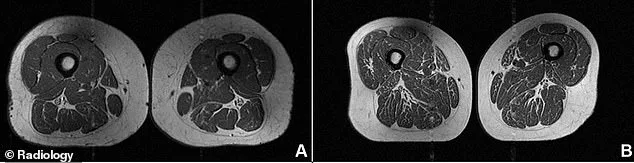

MRI scans comparing two women of similar age and weight highlight the stark differences caused by diet. One woman, aged 61, ate a diet where only 30 percent of calories came from ultra-processed foods; her thigh muscles showed minimal fat infiltration. In contrast, the 62-year-old subject whose leg is pictured in the shocking photos derived 87 percent of her nutrition from these harmful products, resulting in severe muscle degradation.

The urgency of these findings is underscored by advanced imaging. Every participant underwent an MRI of their thighs, where experts graded fat infiltration across the hamstrings, quadriceps, and inner thighs on a strict scale from zero to four. A score of four indicated that fat occupied more than 50 percent of the muscle tissue.

The results, published in the journal *Radiology*, left no room for ambiguity. Individuals with higher UPF consumption exhibited significantly greater intramuscular fat. As the proportion of ultra-processed food in the diet increased, so did the fat levels within the muscle. This correlation held true for all muscle groups studied, but the effect was particularly pronounced when researchers looked at abdominal circumference rather than just body mass index.

The inner thighs, or adductors, emerged as the most vulnerable area, followed by the hamstrings. While the quadriceps showed the smallest impact, the damage was still statistically significant. These findings apply equally to men and women, suggesting a universal risk regardless of gender.